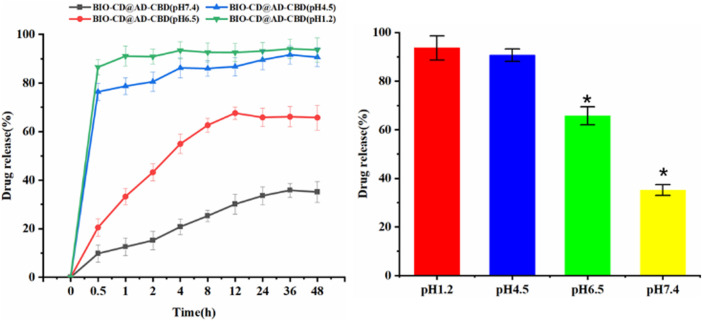

pH-dependent Drug Release Studies

In Vitro Release Property

We tested the effect of pH on drug release, was aimed to observe whether BIO-CD has the targeted ability to deliver chemotherapeutics to cancerous tissues. In order to explore the drug release laws at different pH values (pH 7.4, 6.5, 4.5, and 1.2), four buffer solutions were used to simulate the micro environment of normal human tissues, tumor tissues, organelles and gastric juice at 37°C. After 1 h, we observed that the drug release was enhanced at the acidic pH (pH 4.5 acetate buffer and 1.2 HCl) (Figure 10). In addition, the drug release under pH 6.5 and 7.4 phosphate buffers were further tested. We observed AD-CBD was released suddenly at acidic pH, while CBD was released lower at pH 7.4. Although the guest was relatively stable in the bloodstream (∼pH 7.4), it rapidly released in the weakly acidic micro environment of tumor, which indicated that this pH-mediated drug release mode was important for the designation of controlled drug delivery system. In addition, we recorded the stability of AD-CBD/BIO-CD in different pH media by UV-vis spectra. Supplementary Figure S5 UV-vis spectra indicated that there was no wavelength shift in pH 7.4 and 6.5, but shift in pH 4.5 and 1.2. Therefore, we could conclude that AD-CBD/BIO-CD can remain stable relatively in human plasma (∼pH 7.4) and cancer tissue (∼pH 6.5).